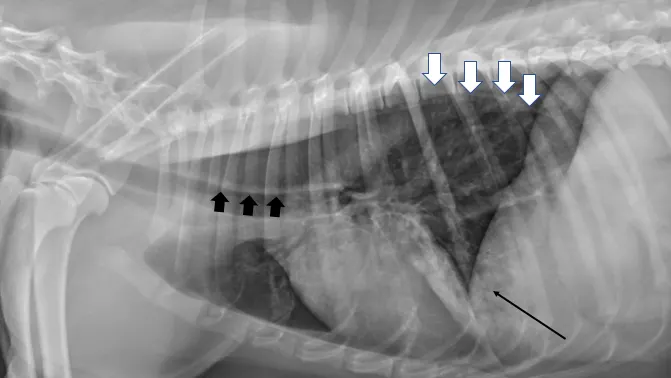

Thoracic radiography is important for diagnostic evaluation of patients with myasthenia gravis (Figure). Dogs with this disease have a high incidence of megaesophagus, as the esophagus contains skeletal muscle throughout its length. Risk for aspiration pneumonia is high and can contribute to neuromuscular weakness, impacting treatment.11

Left lateral radiograph of a dog with myasthenia gravis. The esophagus is diffusely dilated with gas (white arrows), creating a tracheal stripe sign along the dorsal margin of the trachea (wide black arrows). Focal opacity with alveolar pattern in the ventral lung field (thin black arrow) is consistent with aspiration pneumonia.

Megaesophagus has important implications for nursing care; patients should be maintained in an upright position during and after feeding. Megaesophagus may not resolve with treatment despite clinical improvement in muscle weakness.3 Supportive care in patients with esophageal dysfunction is important to avoid nutritional deficiencies and dehydration that can further compromise weakness. Construction or purchase of a chairlike device that supports the dog in a vertical position while eating can help facilitate management. Nursing care and owner education are essential for successful management.

Thoracic radiography can also be used to screen for a cranial mediastinal mass. Thymoma has been associated with myasthenia gravis and can affect case management,3,4,11 as removal may be warranted. Thymectomy in patients with thymoma-associated myasthenia gravis can improve or resolve clinical signs.12 Cats have a higher incidence of concurrent cranial mediastinal masses than dogs.<sup3 sup>